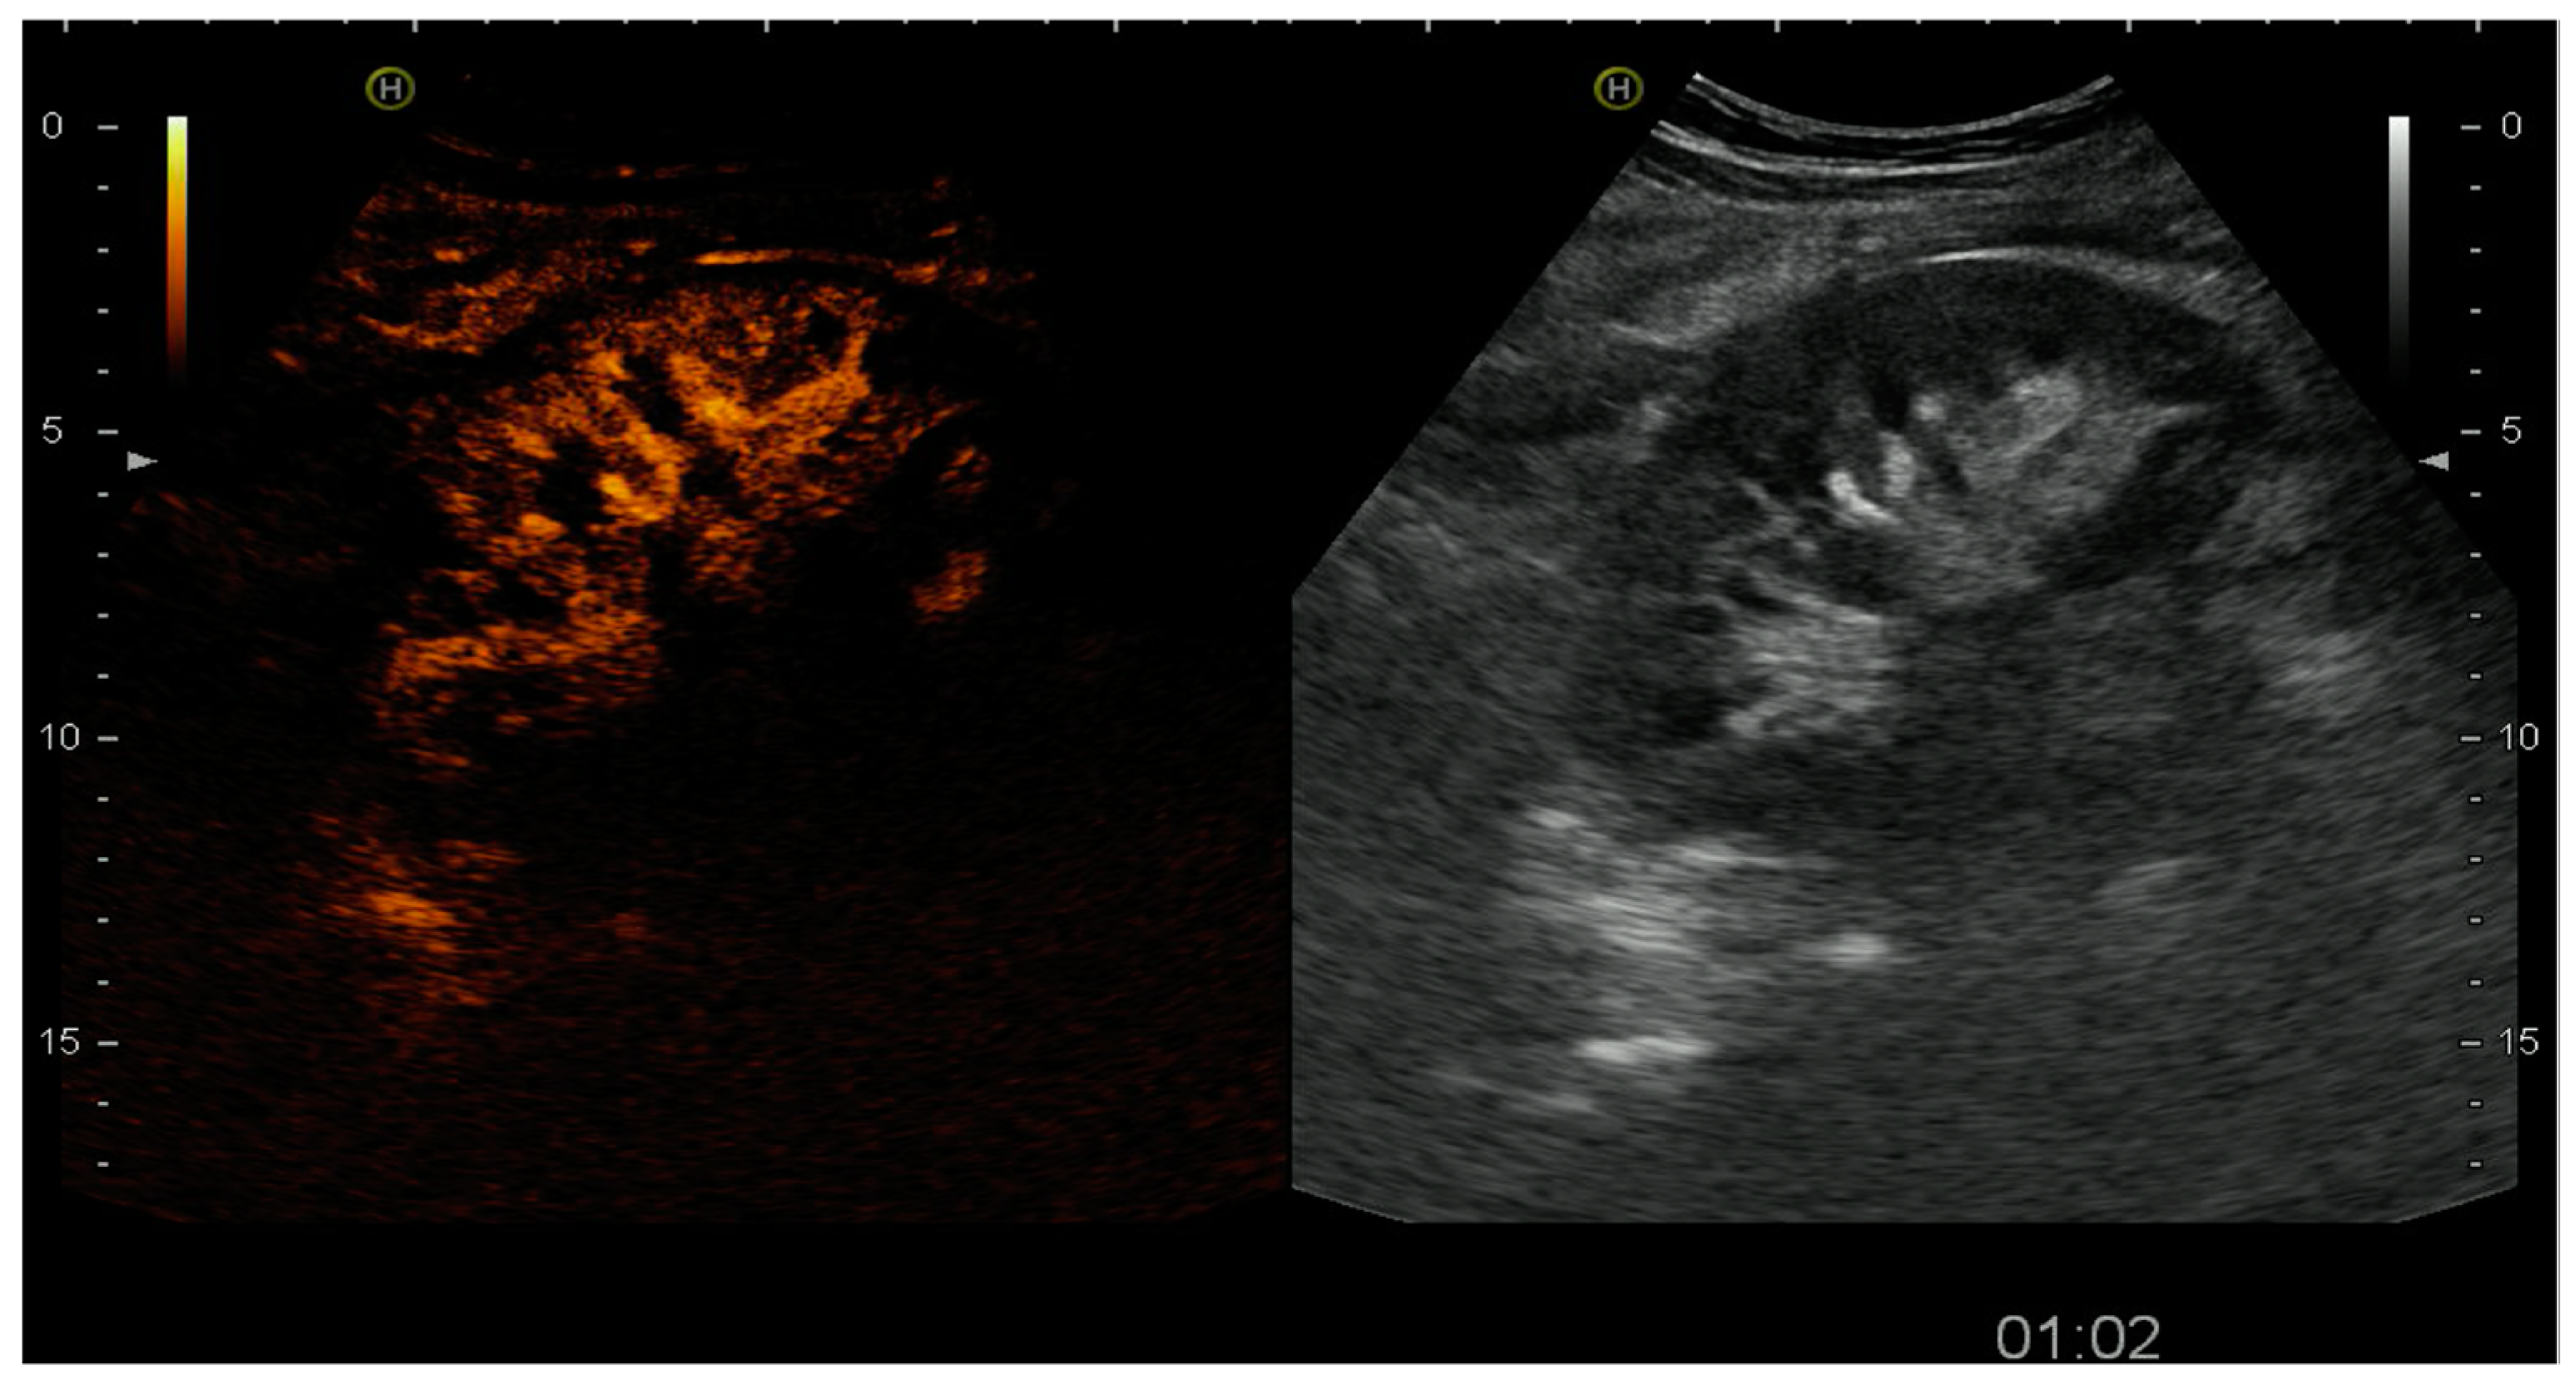

4.1.1. Arterial Thrombosis